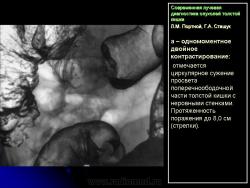

В 1961 г. Wellin предложил методику рентгенологического исследования толстой кишки, названную автором одномоментным двойным контрастированием толстой кишки (ОДКТК). Основное отличие ее от классической ирригоскопии состоит в том, что для исследования толстой кишки используется значительно меньшее количество бариевой взвеси и сразу же, по мере ее введения в дистальные отделы кишки, дальнейшее продвижение осуществляется специальным одноразовым устройством с помощью воздуха, вводимого под контролем рентгенотелевидения с учетом клинических особенностей пациента. Опыт многих исследователей и наш личный опыт указывают, что такие предосторожности при исследовании обусловлены не возможностью осложнений, а тем, что нередко быстрое контрастирование кишки может вызвать спазм отдельных ее участков и тем самым уменьшить его эффективность. Как правило, для исследования всех отделов толстой кишки, так же как и приирригоскопии, применяется стандартизованная методика с использованием тех же пяти проекций. Фиксация изображения осуществляется на рентгеновскую пленку средних размеров 18 х 24, 24 х 30 см. Основными достоинствами ОДКТК следует считать его высокую диагностическую эффективность, методическую простоту и возможность использования при скрининговых обследованиях групп риска по раку толстой кишки. В ОДКТК удачно сочетаются фазы “тугого” наполнения и двойного контрастирования – основные элементы, позволяющие фиксировать внутристеночную инфильтрацию кишки в ее начальных проявлениях с помощью определения состояния контура кишки и толщины стенки. Двойное контрастирование позволяет получить исчерпывающую информацию о слизистой кишки, которая при отсутствии в ней изменений (небольших полиповидных образований, изъязвлений и др.) должна быть полностью разглажена и лишена складчатости (рис. 1).

При одномоментном двойном контрастирова нии толстой кишки:

1) утолщение стенки, неровность контура и сужение просвета одного из участков кишки (рис. 5);